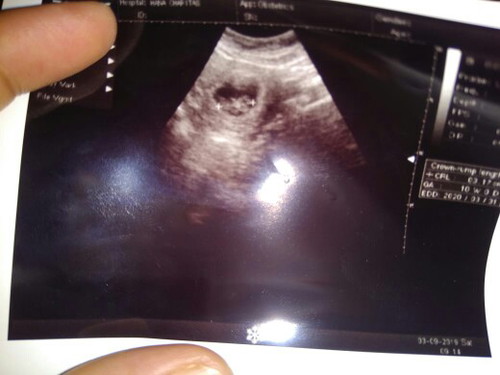

usg pertama

puji Tuhan dedeknya sehat???

10w bund